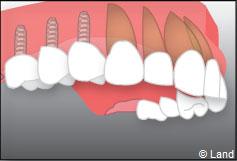

Exemple de 3 dents manquantes remplacées par 3 couronnes sur implants.

Pose des piliers prothétiques et des 3 couronnes scellées.